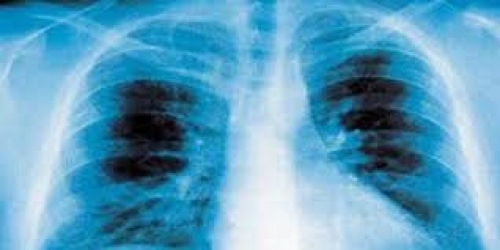

أعراض التهاب الرئة ذكر تقرير نشره الموقع الأمريكى "مايو كلينيك"، علامات وأعراض الالتهاب الرئوى فهى تختلف من خفيفة إلى ش...